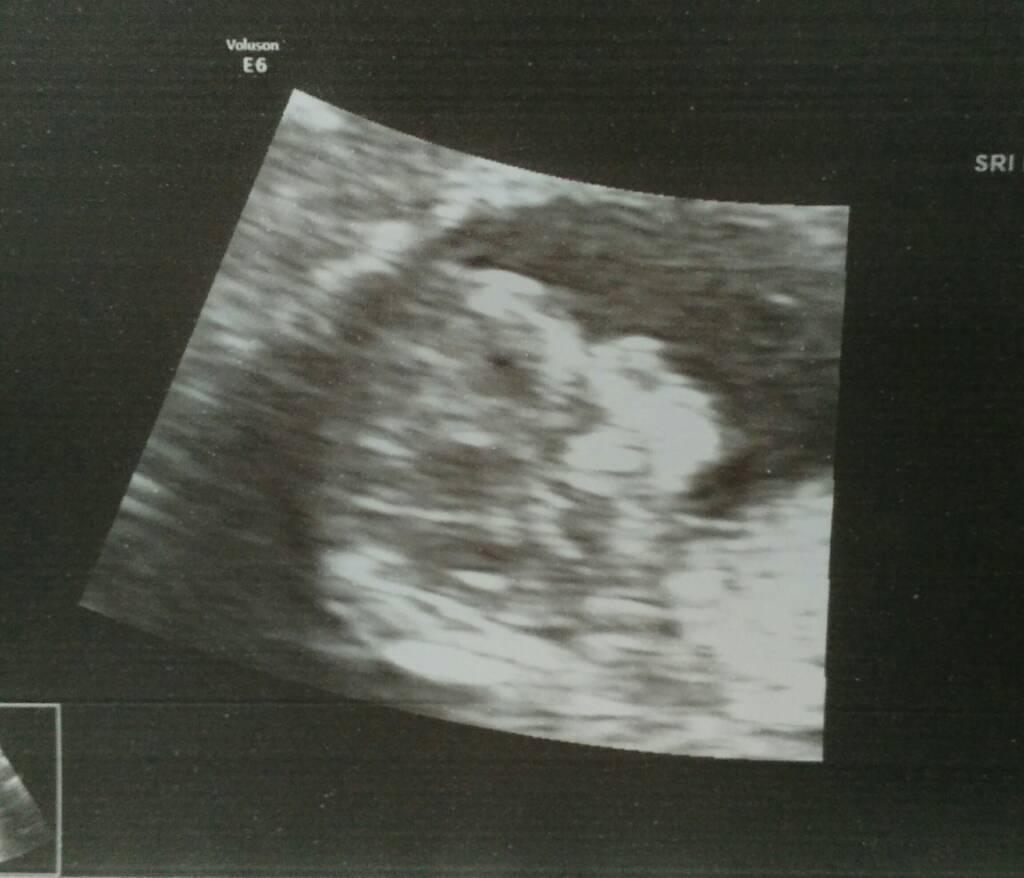

Moje kochanie zdrowe! Kość nosowa widoczna, przezierność 1,3 mm, rączki i nóżki są, narządy wszystkie są, serducho bije prawidłowo!

Płeć nieznana, za wcześnieMaluszek jest o prawie tydzień starszy, z miesiączki 11t5d, a usg 12t4d i mierzy całe 6,07 cm! Termin porodu to 12.08. (a wcześniej było 18-20.08.) Tak słodko spał, że trzeba było go do badań obudzić. Aż się po wszystkim popłakałam ze szczęścia..! [emoji173] [emoji173] [emoji173] [emoji173]